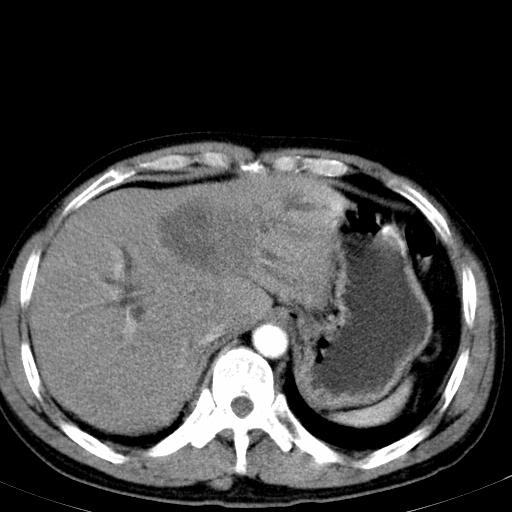

患者上腹部疼痛一月余,伴巩膜黄染;

实事求是的说,强化效果很一般,重点部位应重点观察,但有一点可以明确:肝门部胆管细胞癌。

考虑肝左叶胆管细胞癌侵犯肝门区并肝内胆管及肝总管扩张。

肝左叶肿块清度增强,所在的叶胆管扩张。考虑胆管细胞癌。

考虑肝左叶胆管细胞癌侵犯肝门区并肝内胆管及肝总管扩张、肝门淋巴结肿大。